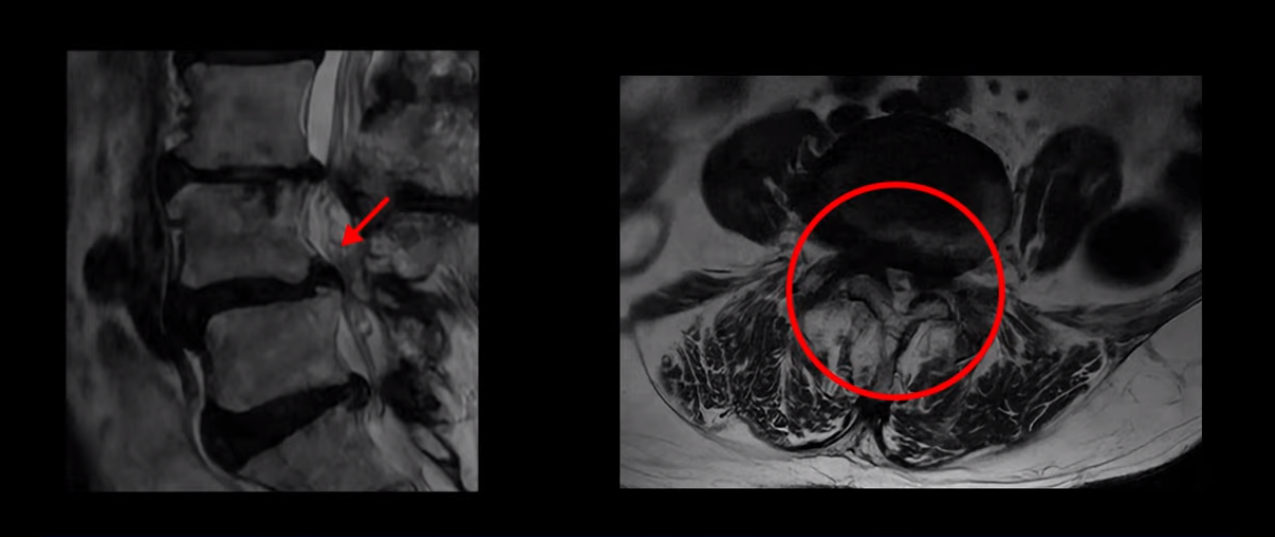

제가 먼저 이분 MRI를 보고 설명해 드린 후 어떻게 이런 분들을 수술 없이 허리 기능재활치료로 호전시킬 수 있는지 자세히 설명드리겠습니다. 이분 허리가 보시다시피 여러 마디가 퇴행되어 있고

4번 5번에는 뼈가 밀려 나간 전방전위증도 있습니다.

4번 5번 마디를 자세히 보면 심한 중심성 협착이 있어서 신경 구멍이 매우 좁아져 있습니다.

또 신경 가지가 빠져나가는 추간공도 매우 좁아져 있습니다.